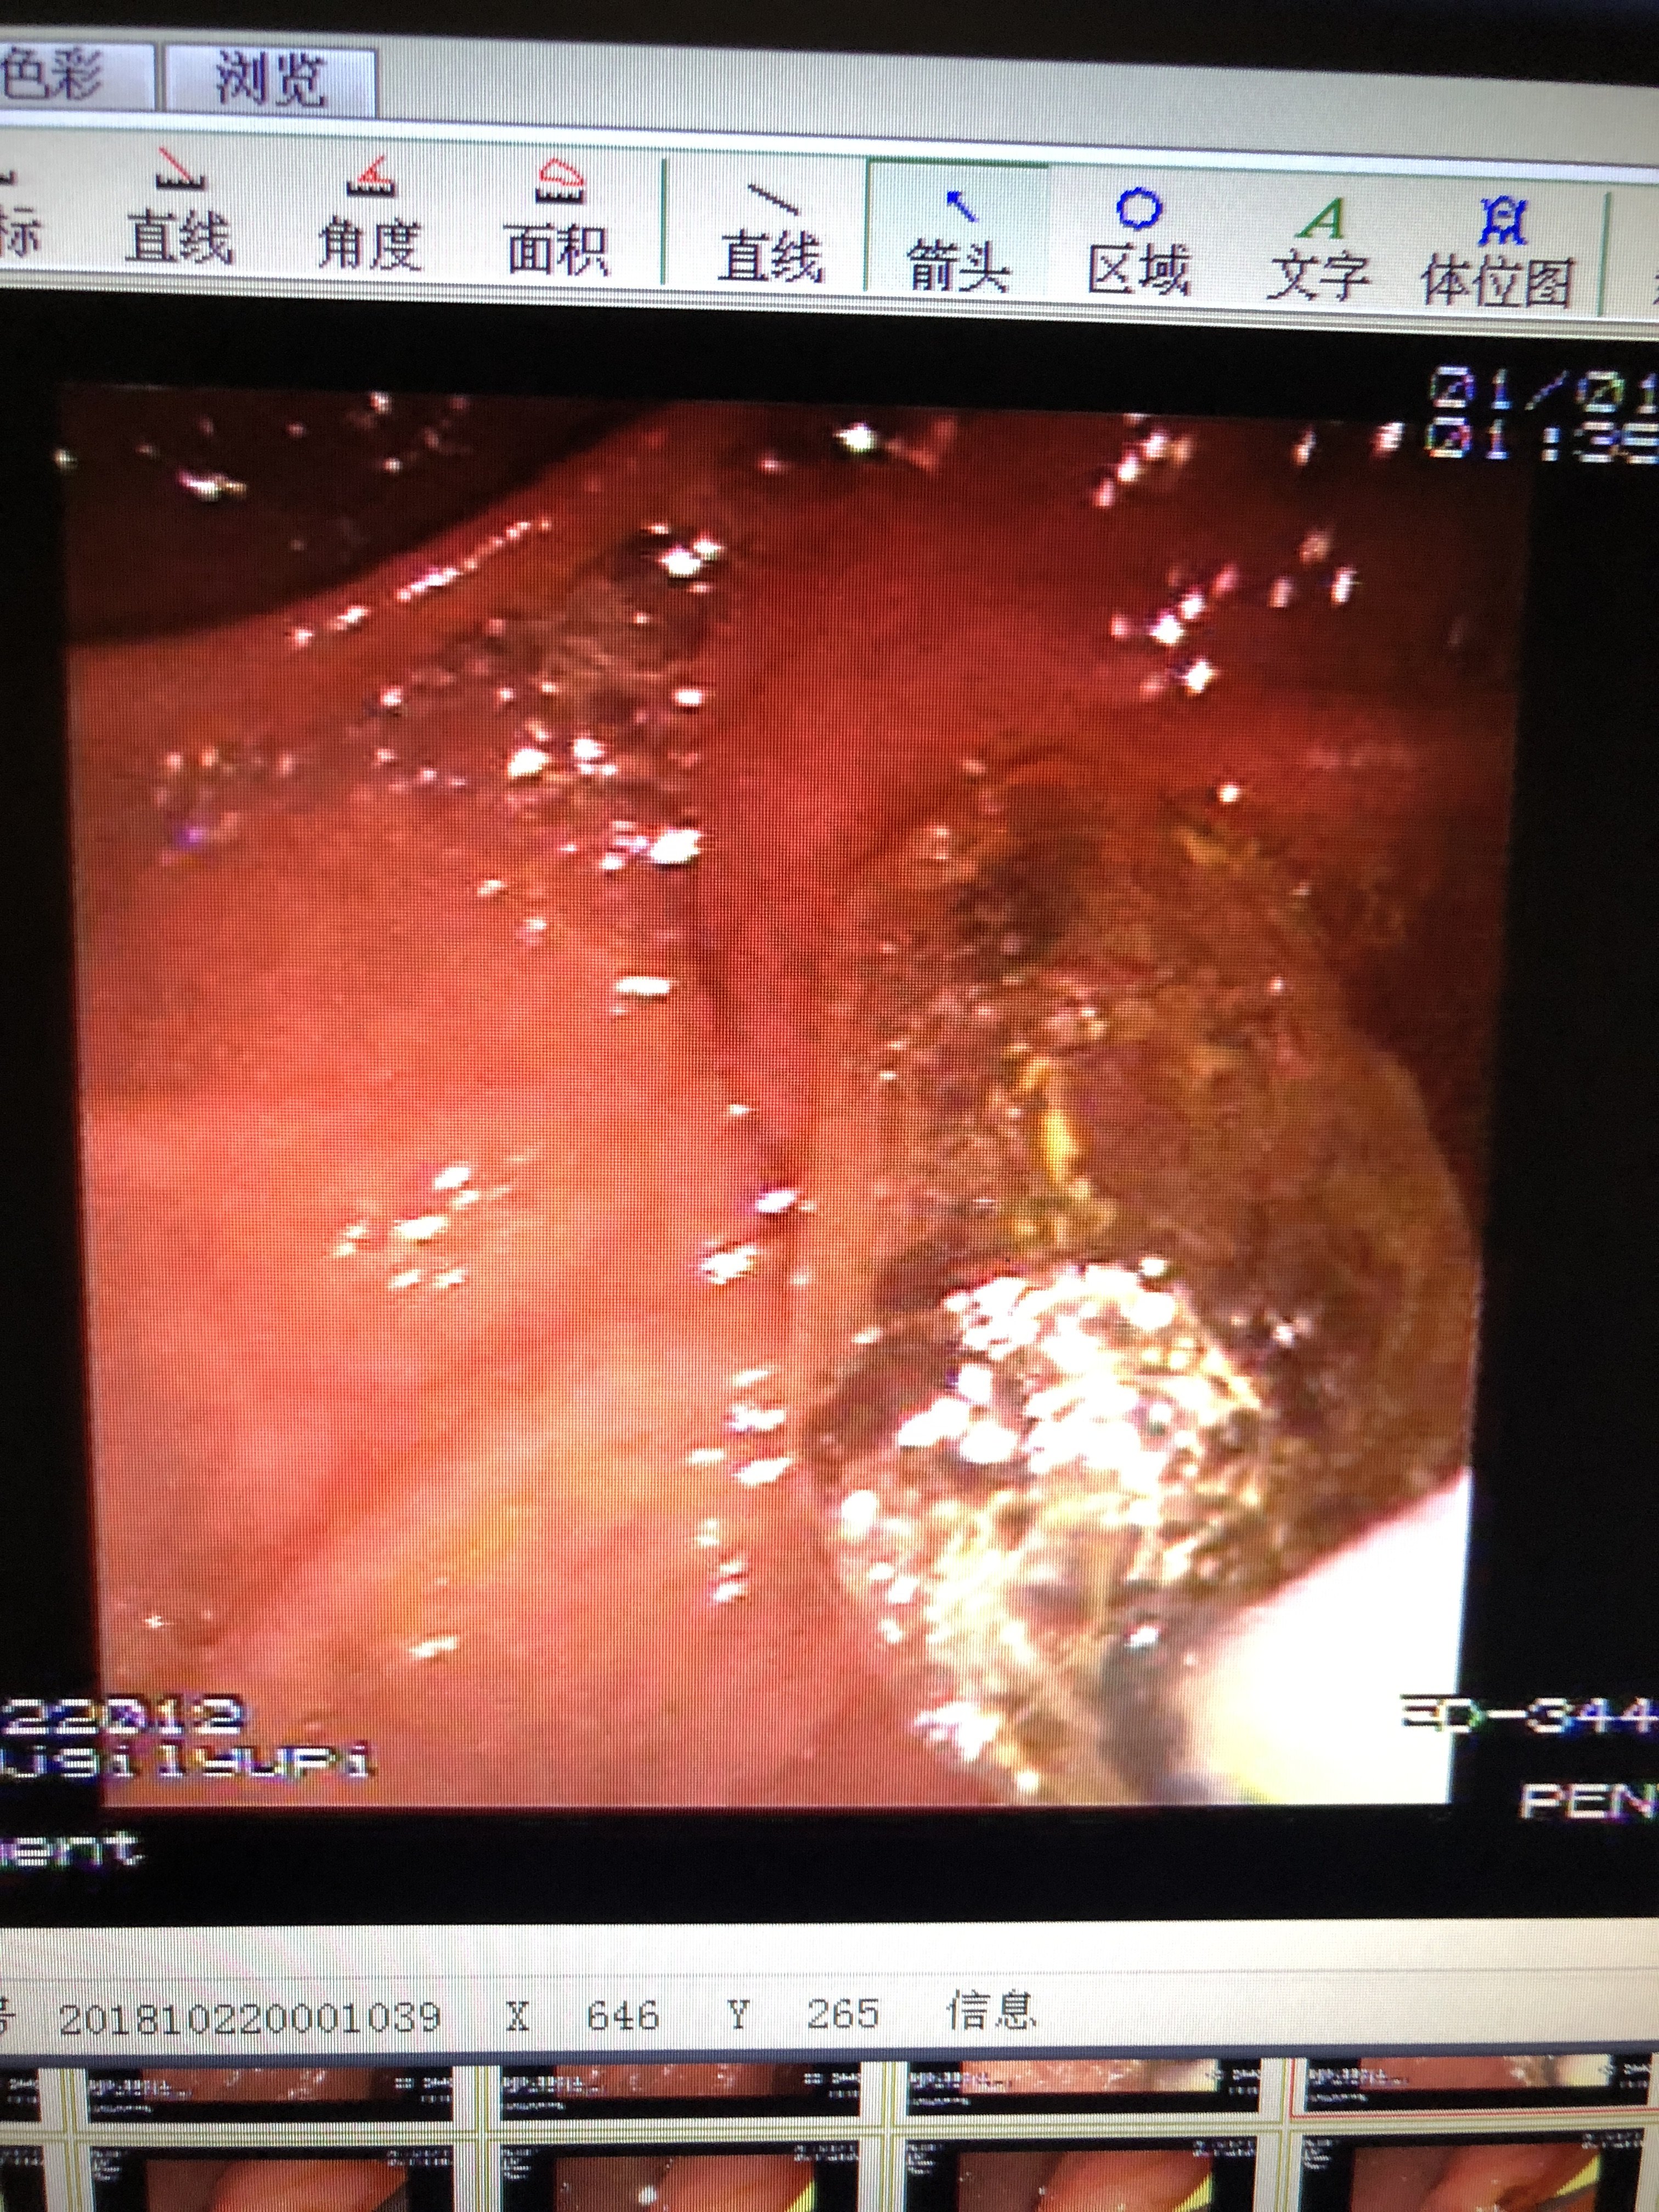

胆管下端狭窄即缩窄性乳头炎伴胆管扩张并

3024x4032 - 2433KB - JPEG

7种胆道系统疾病影像学诊断